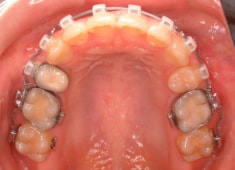

治療前

治療開始時